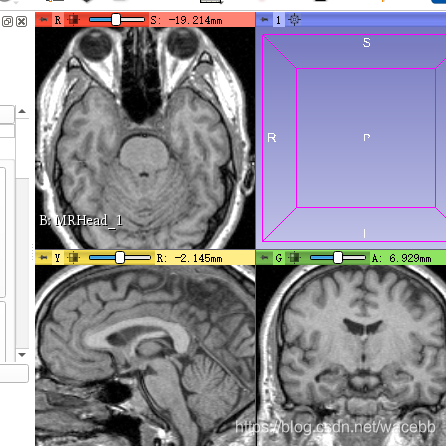

下载完成就会自动显示再右边:

接下来,我们来了解下如何对数据进行显示调整!

首先我们可以通过鼠标滑轮来调整显示,或者可以直接移动上面的滑轮。

长按左键移动可以调整数据的亮度,

长按右键移动可以缩放,也可以ctrl+滑轮来调整大小。

shift +左键 就可以移动位置:

shift + 左键移动 则可以再另两个切片上显示相应位置。